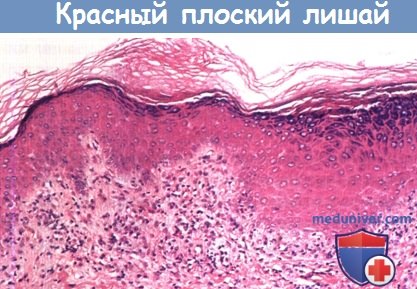

Фото Красного Плоского

Фото Красного Плоского 103 фото